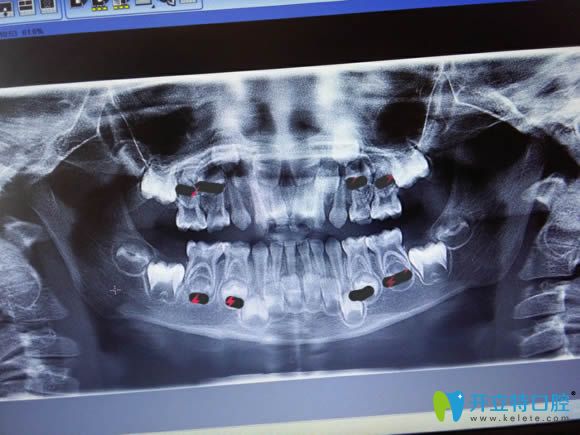

兒童牙片顯示圖